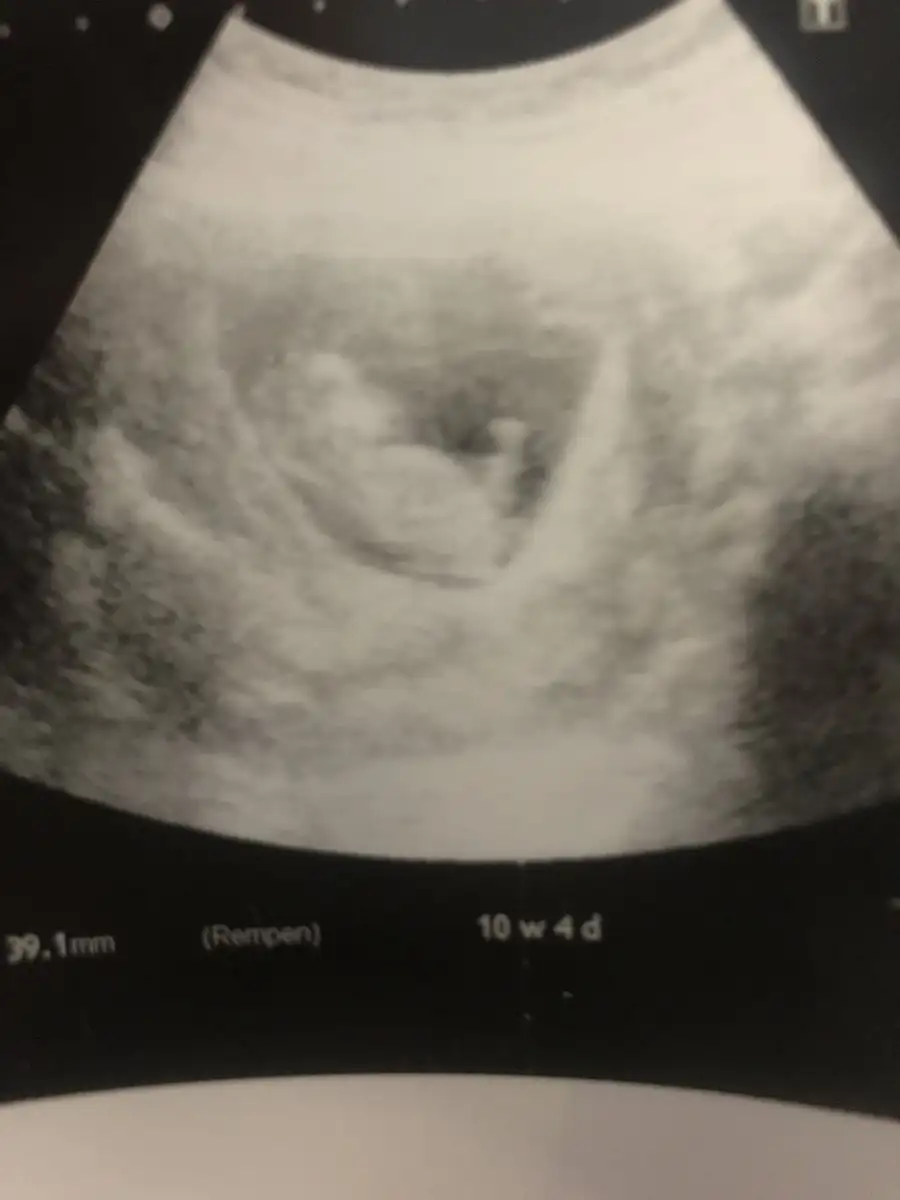

Çok tatlı kıpır kıpır bakmaya doyamadım, Allah’ım isteyen herkese versin, olanlarada sağlıklı ömür versin